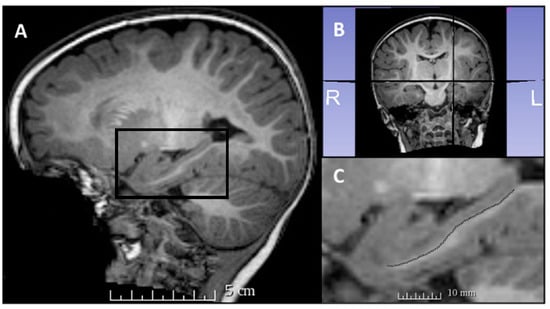

Hippocampal dentation, present in the CA1/subiculum of the human hippocampus, was assessed in this study by counting the number of hippocampal dentes for the left and right hippocampus of each participant individually (Figure 1, Figure 2 and Figure 3). Hippocampal dentation was visualized in the sagittal plane, using all available sagittal slices to determine the total number of dentes for each hippocampus. Hippocampal dentation was described previously in adults using ultra high-resolution structural neuroimaging (HR-MICRA technique with 0.5 × 0.5 × 0.75 mm3 resolution) []. While a previous study described hippocampal dentation in terms of both quantity and prominence, in this study, dentation was measured by quantity only, adapted due to the reduced visibility of dentation and the SRLM layer (stratum radiatum, lacunosum, and moleculare) in this scan resolution. See Beattie and colleagues (2017) for more detailed methodology on the previous study. In the current study, right and left hippocampal dentes were counted for all participants by a researcher trained in hippocampal anatomy (J.F.B.). The main analyses were conducted using these results. Approximately 25% of scans (n = 24) were counted by two additional trained researchers (T.A.C. and R.Q.J.) to assess inter-rater reliability. All raters were blinded to participant variables, including age, while counting dentation.

Figure 1. Hippocampal dentation visible in a 7-year-old participant. (A) Sagittal view, with the left hippocampus shown in the black box. (B) Coronal view, with corresponding sagittal placement of the viewing panes in (A,C). A larger image of the hippocampus is visible in (C), with black arrowheads indicating three dentes visible in this sagittal slice. All available sagittal slices were used to count the dentes for each hippocampus.